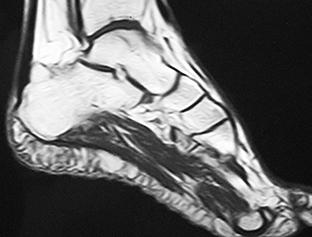

La fascitis plantar es una patología de las partes blandas y su diagnóstico no se puede basar únicamente en la imagen radiográfica de un espolón del calcáneo o calcificaciones bien estén en la inserción del tendón de Aquiles o en el origen de la fascia plantar [46]. Por eso, la ecografía es el método de diagnóstico de referencia para la evaluación de los trastornos de la fascia plantar [47], pues su precisión y fiabilidad son comparables a la RM y es más rápida, económica y accesible [30][44-49] (Figura 2)

Figura 2A

Figura 2B

Figura 2C

Figura 2. A) Imagen ecográfica de la aponeurosis plantar. B) medición del grosor de la aponeurosis plantar. C) RM sagital del pie